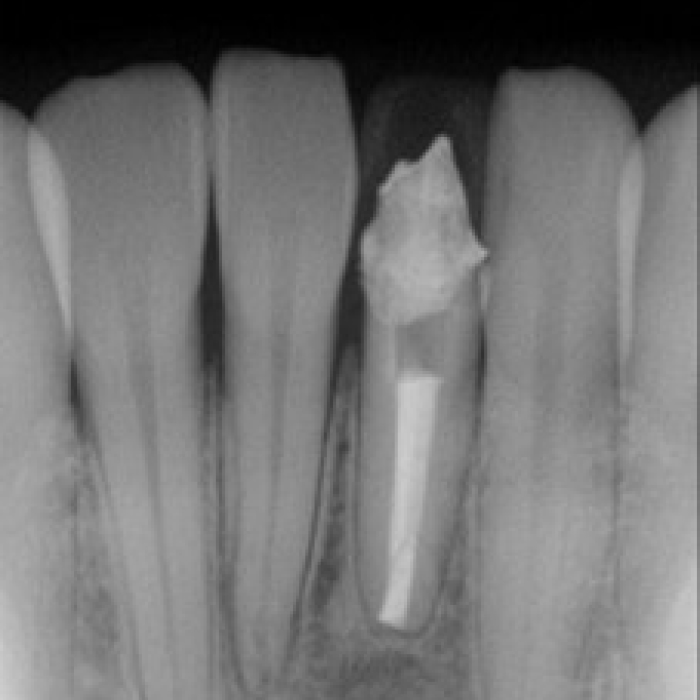

신경치료 전후 사례

• 치료 전

치료 후